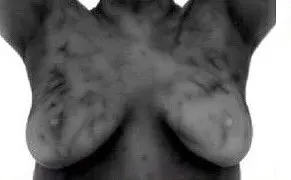

Breast Thermography Conditions & Case Studies

Conditions Breast Thermography Helps Monitor

Breast thermography provides a non-invasive way to evaluate physiological patterns that may support early awareness and ongoing monitoring of breast health. It can be used as part of a broader approach to understanding:

Thermography can help visualize the physiological patterns associated with hormonal influence, such as increased vascular activity or mottling related to estrogen dominance.

Inflammatory Breast Cancer (IDC)

IBC is rare but aggressive from of breast cancer that often does not present as a lump, making early recognition of symptoms important.

Possible Signs of IBC include:

- Sudden enlargement of one breast

- Pink, red or bruised appearance

- Increased warmth

- Skin dimpling or texture changes

- Nipple inversion

- Tenderness or discomfort

- Enlarged lymph nodes near the breast or collarbone